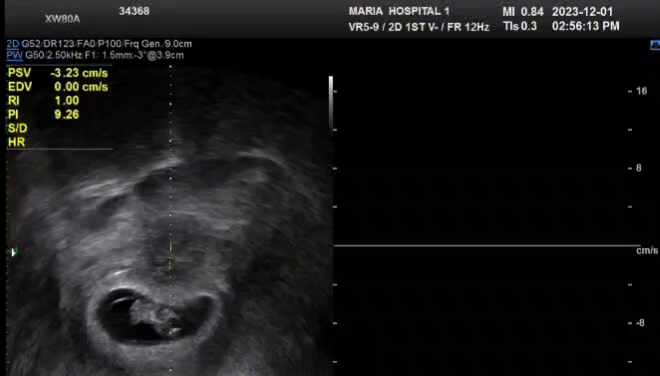

임신 8주, 초음파검사, 임신피검사[상봉마리아에스,허창영원장님]

임신8주차 2023.11.29.수 , 추가약 처방 2023.12.1. 금 임신 8주 진료 프로기노바 아침2알, 저녁2알 식후에...